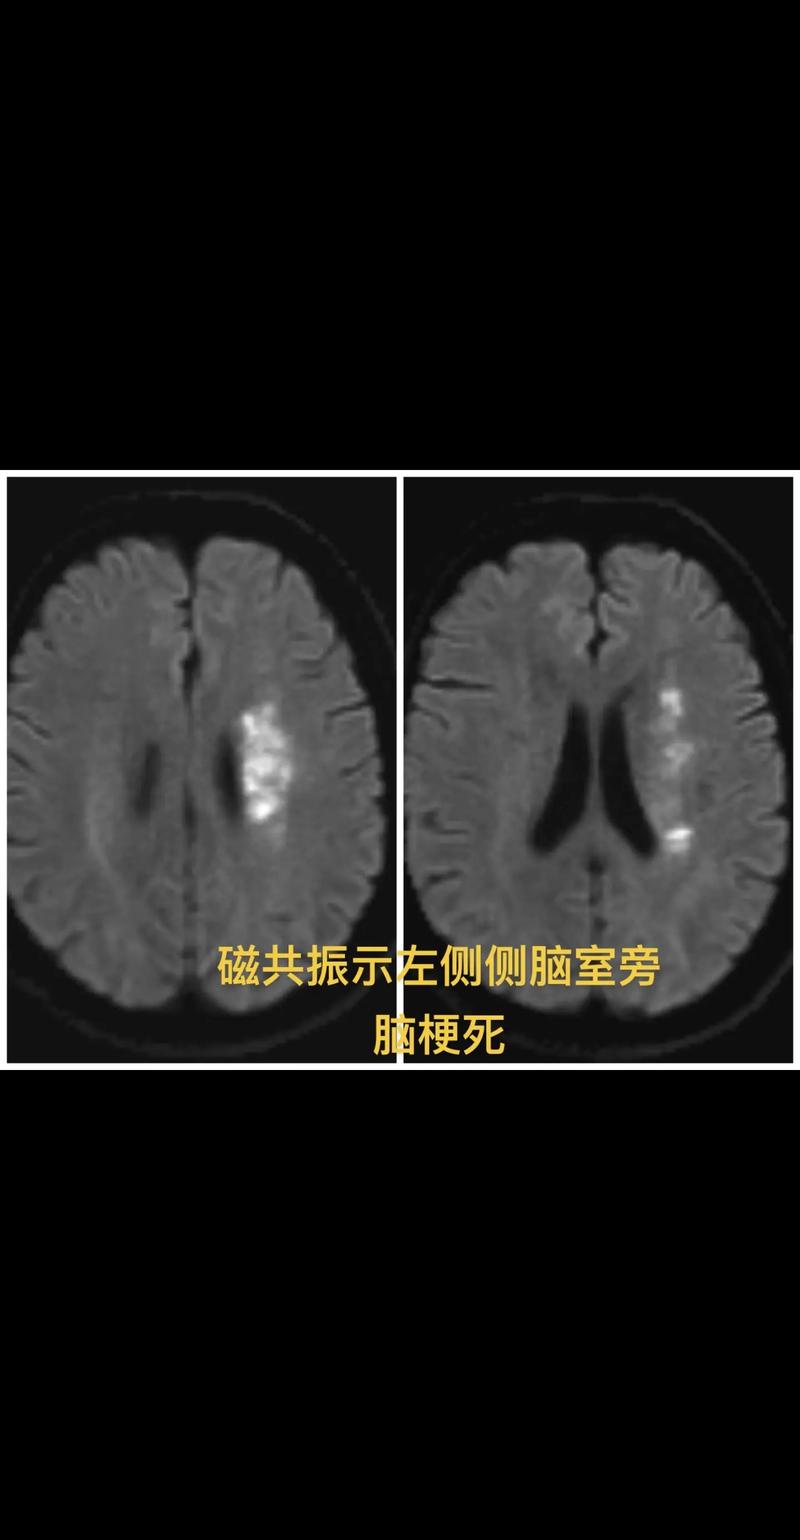

(图片来源网络,侵删)